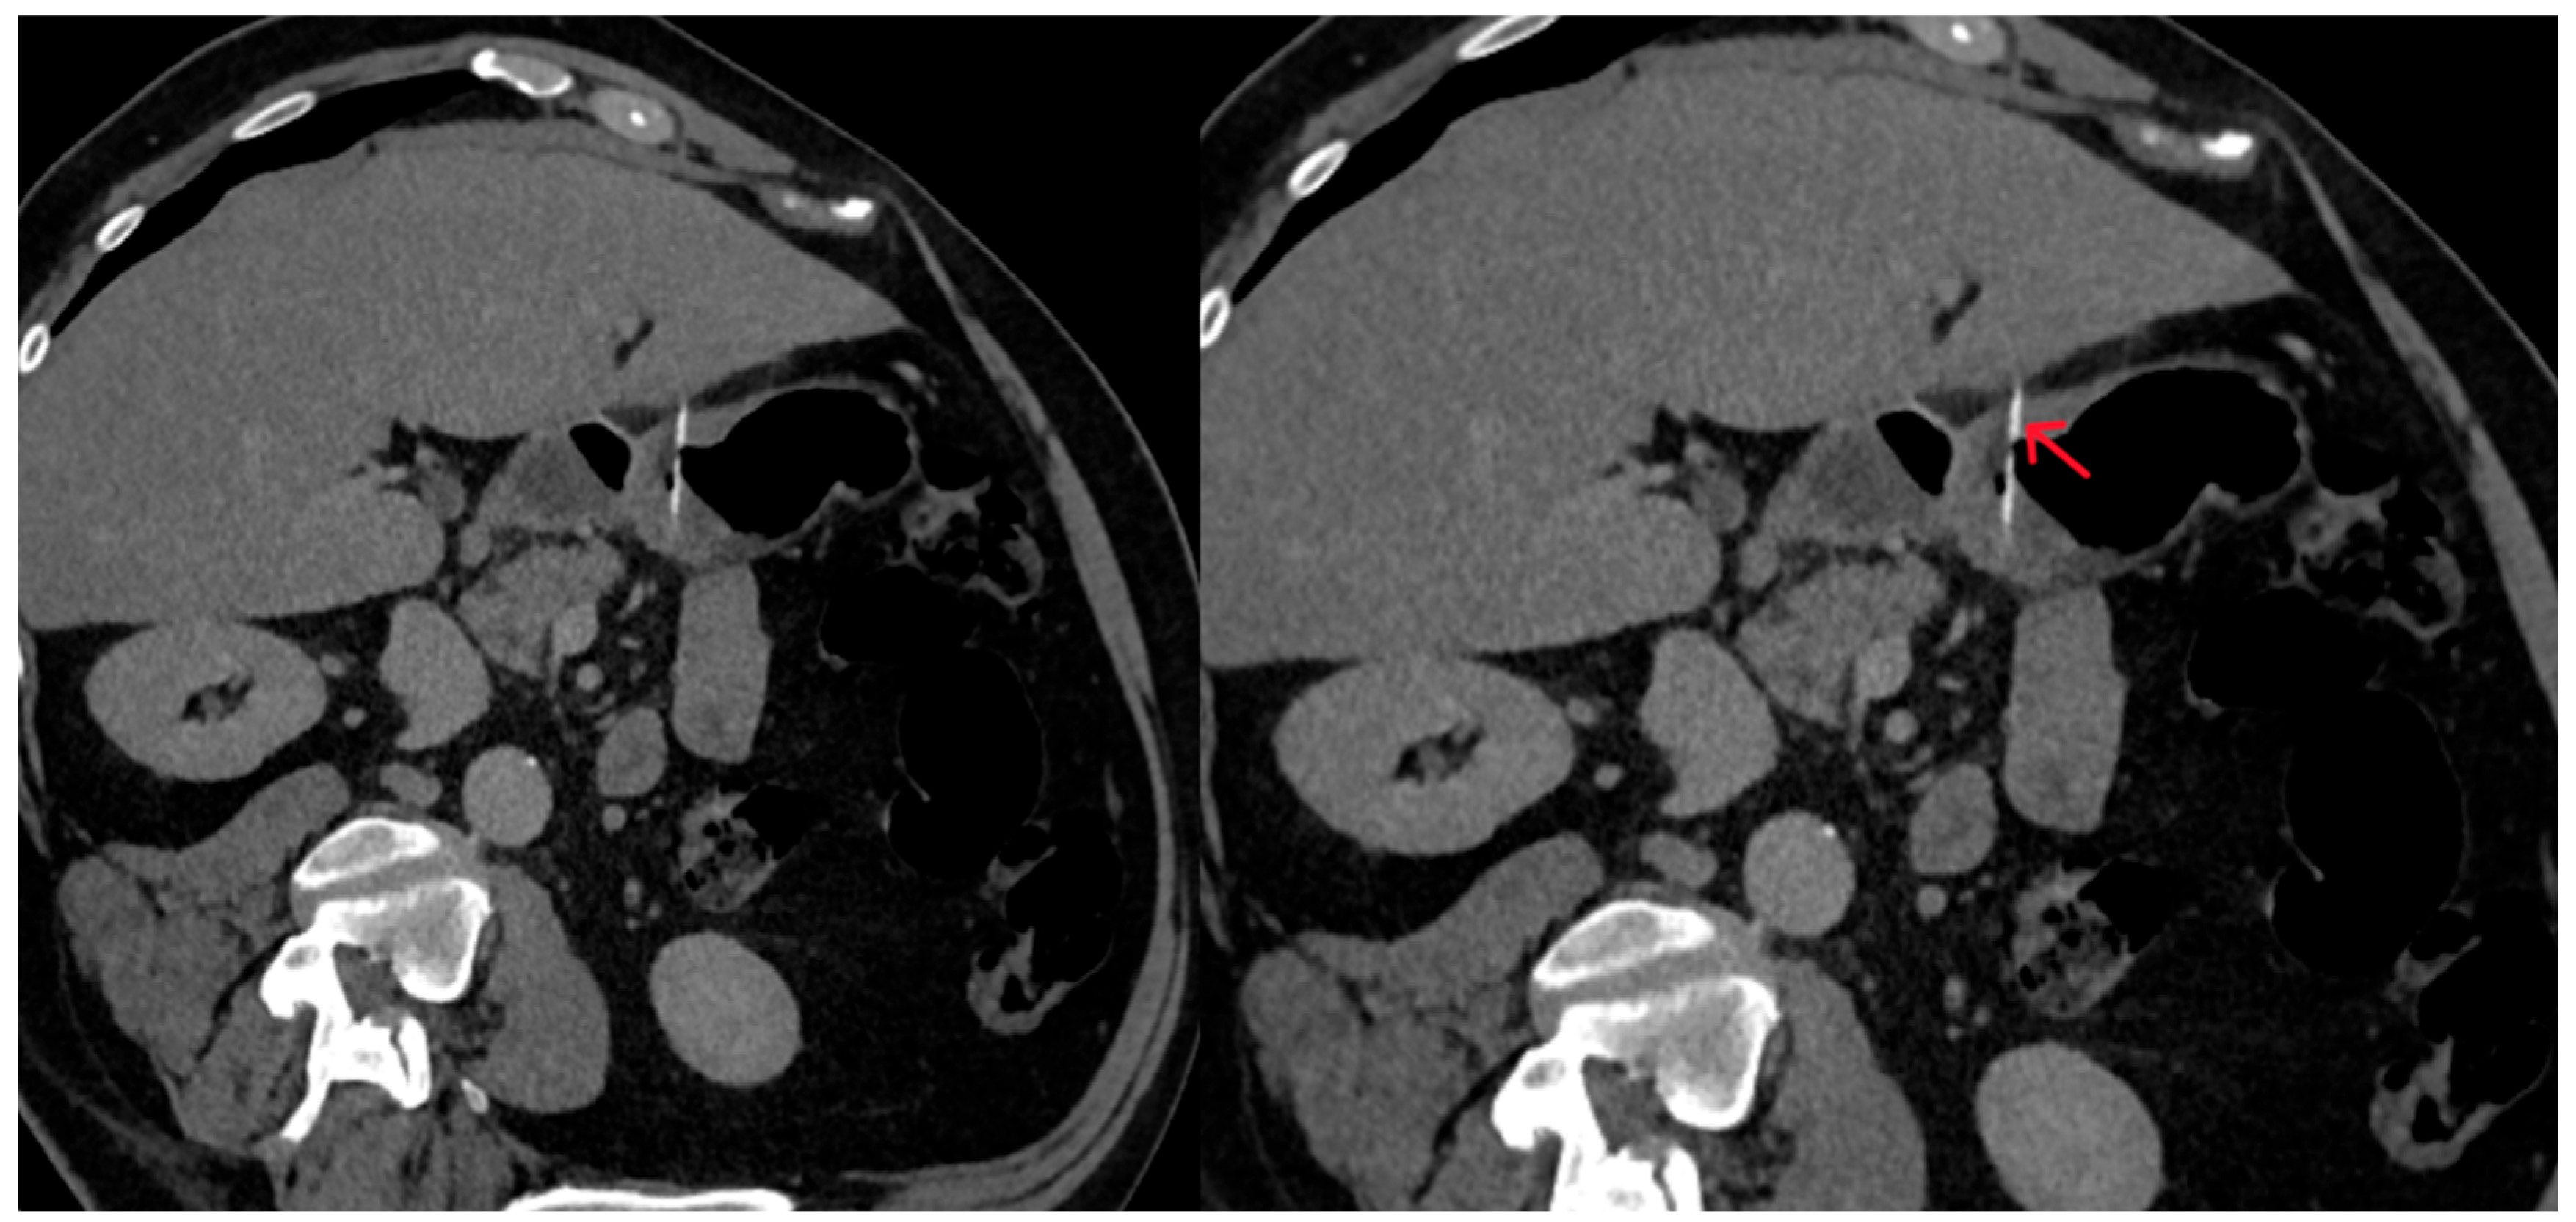

The abdominal CT scan showed a foreign body in the pylorus of the stomach that was penetrating the wall of the stomach (Figure 1). There was also air outside the stomach, along with signs of inflammation in the adjacent adipose fatty tissue (Figure 2 and Figure 3). The diagnosis of perforation of the stomach wall with a foreign body was made, leading to subsequent concealed, local peritonitis.

Figure 1. The foreign body is observed within the stomach lumen, projecting outside the stomach wall margins, suggesting perforation (red arrow).